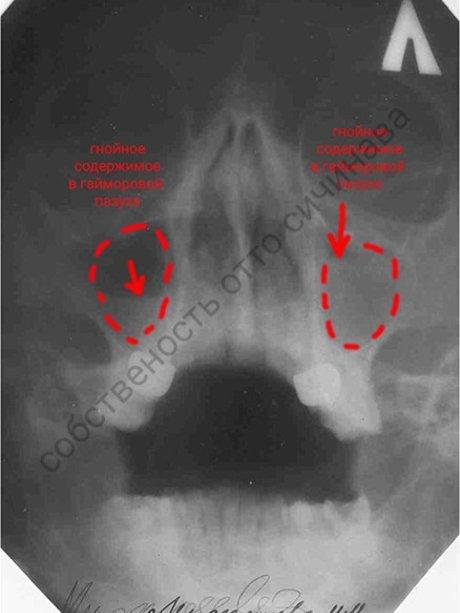

До лечения

Двухсторонний гнойный гайморит. Виден уровень гноя в правой гайморовой пазухе. Левая гайморова пазуха доверху заполнена гноем.